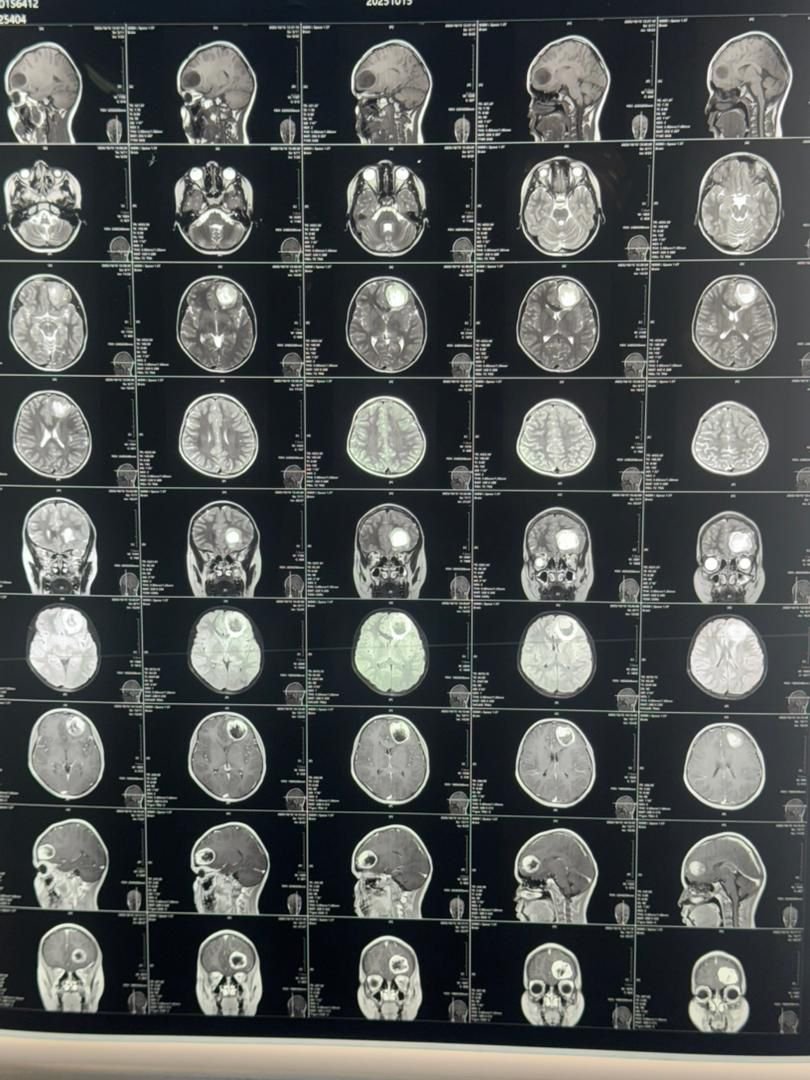

طالبان ساغلیقنی سقلش وزیرلیگی بوگون یکشنبه ۷- جدی، بیانات نشر قیلیب، بلخ حوزوی کسلخانهسی (ابوعلی سینا کسلخانهسیده) مییه تومورینی آلیب تشلش عملیاتی موفقیت بیلن عملگه آشیریلگنیدن خبر بېردی.

بیاناتگه کۉره، مذکور عملیات ایلکبار بلخ حوزوی کسلخانهسیده عملگه آشیریلگن.

اوشبو عملیات ۱۲ یاشر بیر قیز باله مییهسیده عملگه آشیریلگن.

طالبان ساغلیقنی سقلش وزیرلیگی، مذکور عملیات بیش ساعت دوام اېتگنینی هم معلوم قیلدی.

عملیات بۉلگن قیز باله، مییه توموری باعث آغیر باش آغریغی، کۉنگیل اَینیشی و کۉریش قابلیتی آزهیشیگه دوچ اېکن.